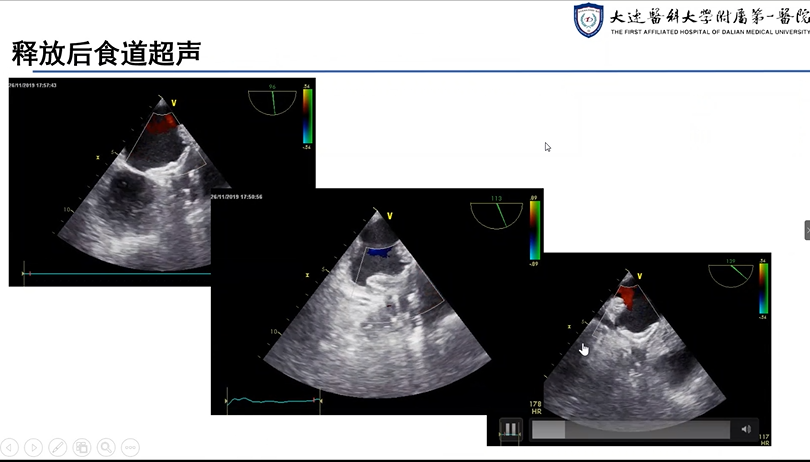

大连医科大学附属第一医院肖宪杰教授分享了两例使用LAmbre™左心耳封堵器系统进行的挑战性案例,并将其对于术中造影时如何排除残存空气以及如何应对常规体位造影成形不佳等问题的解决方案与专家们进行了充分探讨。

《左心耳封堵病例分享》—肖宪杰教授